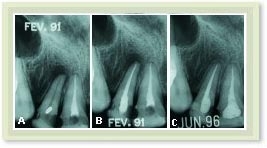

A Dente com polpa infectada e lesão óssea.

B Tratamento de canal realizado em fevereiro de 1991.

C A radiografia tirada 5 anos depois mostra reparo total da lesão, com formação de osso no local onde havia a lesão.